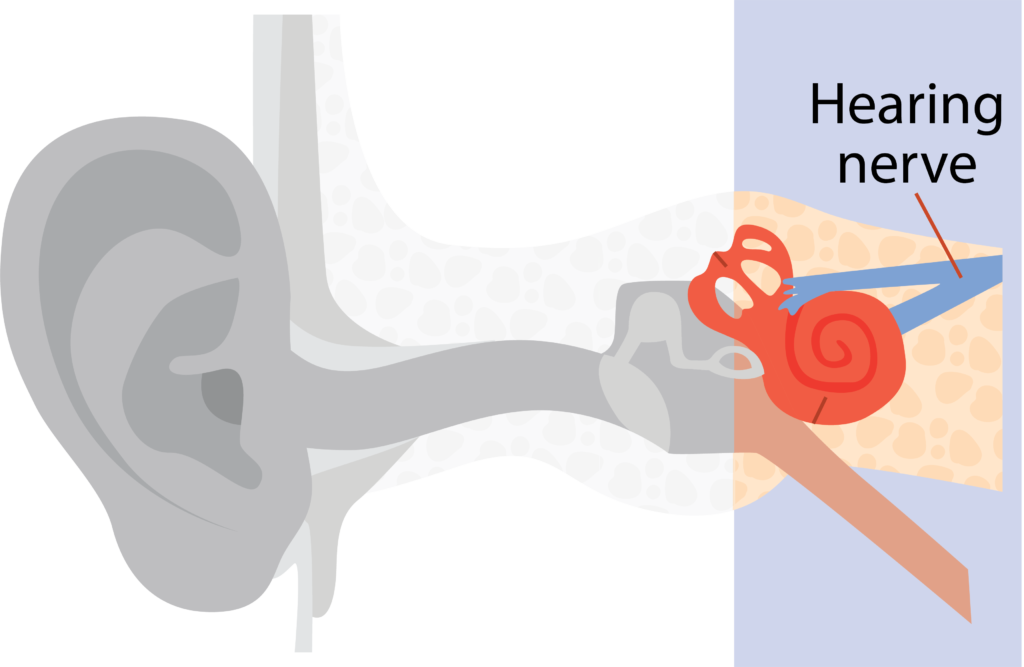

Inner ear

The inner ear changes sounds into electrical signals, which travel from the hearing nerve to the brain.

It is not possible to see the inner ear during screening.